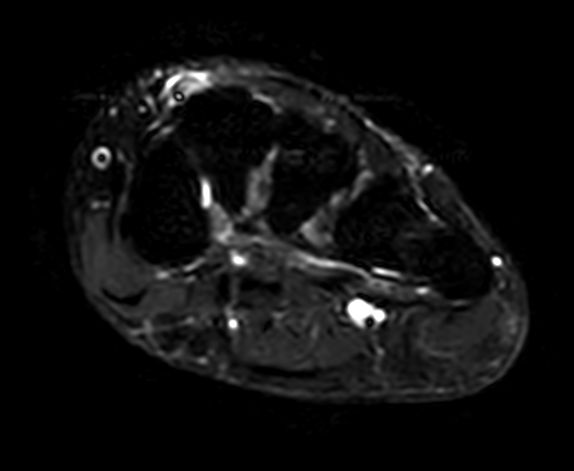

Axial T2w TSE

Axial STIR TSE